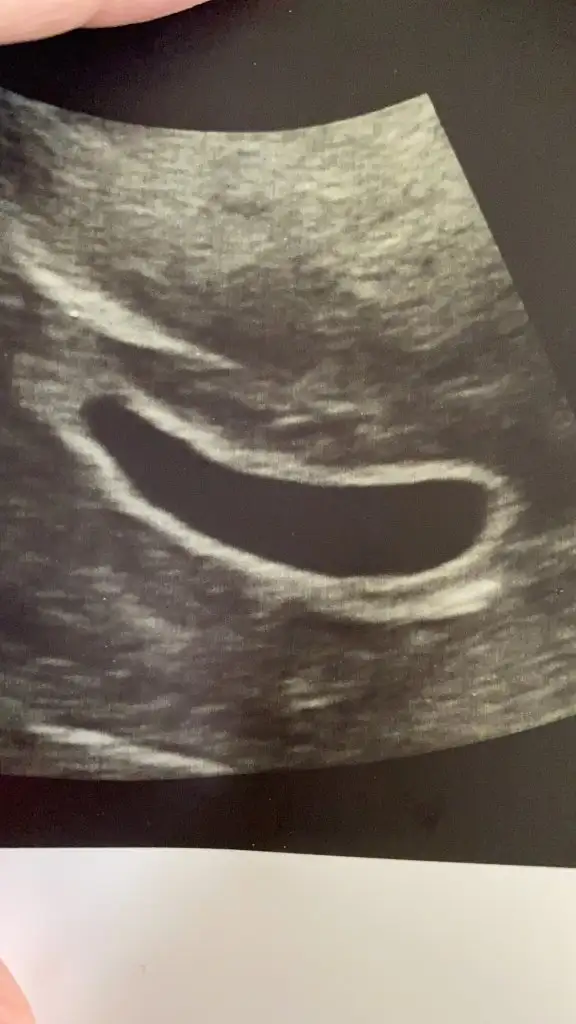

Baya kese büyük canım benim 2 cmlik di senin sanki olacak gibi geliyo bana bebek inşallah olur cnm 8 10 hafta kalp atisi duyulurmus canım senin de embriyo belki olmustur sen ne zmn gitcn kontrole